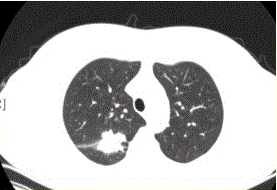

问题 患者女,54岁,无症状,常规体检透视时发现右上肺阴影。既往无结核病史。体格检查阴性。CT结果如下图。 易出现空洞的肺癌类型是

选项 A.鳞癌 B.腺癌 C.未分化癌 D.肺泡癌 E.转移性肿瘤 F.肺类癌

答案 A

解析 A